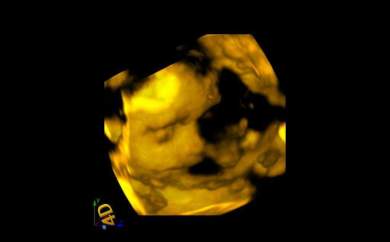

mercedes-eco2Es la última que nos envía sus ecografías. Solo tiene 18 años. Ha conseguido poder pagarse unas ecografías en 4D. Nos las ha enviado a toda la asociación. Se llama Mercemercedes-eco3des y es una de las menores de 20 años que tenemos en los cursos de la asociación. Está tan feliz que se ha puesto a estudiar. mercedes-eco4Viene a todo lo que la convocamos. Y ella también nos hace felices a nosotros. La hemos prometido que le pondríamos sus ecografias en este blog para que lo puedan ver todos los rescatadores Juan Pablo II. Como nos comentó hace dos días, parece mentira que hace 5 meses intentara abortar a su hijo. Hoy empieza su tercer trimestre de embarazo. Asociación MásFuturo